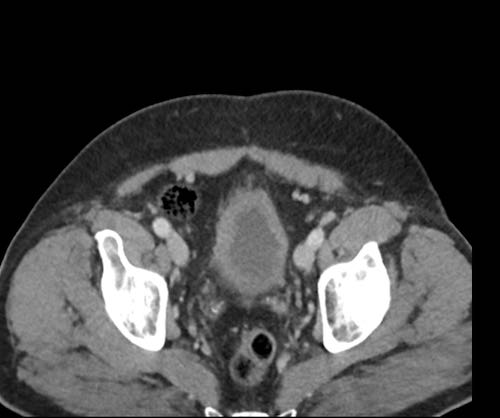

Ở vùng chậu, vị trí quan trọng nhất là túi cùng trực tràng-tử cung và trực tràng-bàng quang (túi cùng Douglas).

Đôi khi có thể thấy di căn khối u lan ra phía trước bàng quang, nhưng không xâm lấn thành bàng quang, do bàng quang là cơ quan nằm ngoài phúc mạc.

Tuy nhiên, vòm bàng quang phía trên và ống niệu rốn được ngăn cách với khoang bụng bởi một lớp phúc mạc thành, tạo thành đích tiềm năng cho các tế bào khối u.

Đặc biệt khi bàng quang đầy, các tổn thương di căn phúc mạc có thể được quan sát thấy ở phía trước bàng quang, áp sát thành bụng trước.

Đây không phải là bệnh lý quanh bàng quang, vì khoang quanh bàng quang nằm ngoài phúc mạc và không thông với khoang trong phúc mạc.